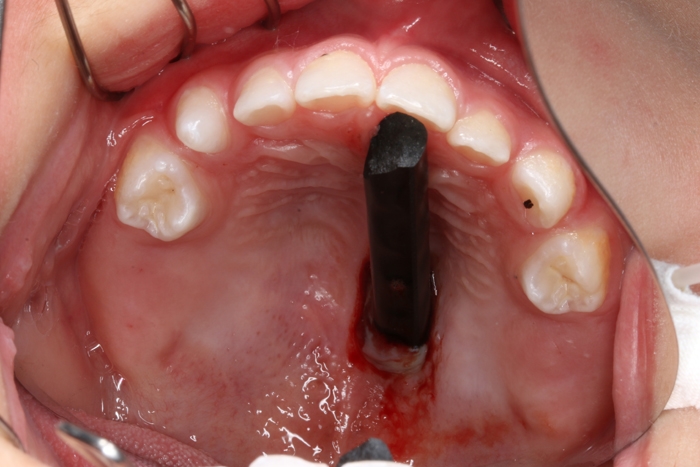

驚!半截筷子直插口腔上顎

??? 當(dāng)日下午,楊先生家兩歲的兒子在家中拿著一根筷子蹦蹦跳跳,四處跑動,看到有燒熟的玉米就自己將玉米插在筷子上,邊玩耍邊吃。一不小心,孩子一個趔趄摔倒在地,當(dāng)家人跑過去扶起他時,發(fā)現(xiàn)筷子斷成了兩截,其中一段插在了孩子的口腔里。孩子撕心裂肺的哭聲,插在寶寶口腔上顎的筷子讓他們一家人束手無策。在當(dāng)?shù)蒯t(yī)院醫(yī)生的建議下,楊先生立刻將孩子送到了衢州市人民醫(yī)院就診。

??? 據(jù)接診的口腔科徐醫(yī)生介紹,患兒來院時筷子戳入口腔上顎的深度不明,貿(mào)然拔出可能有出血不止的風(fēng)險,因此立即安排患兒做了急診CT,在確定筷子位置和深度的情況后,急診為患兒行顎部裂傷清創(chuàng)縫合術(shù)。

術(shù)前